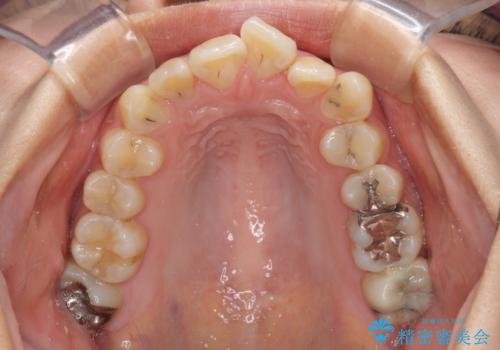

- 虫歯が多く、磨きにくい歯並びを改善したいとのことで来院された患者様です。

歯列は叢生が認められる程度でしたが、やや前突感があったので、少しでも口が閉じやすくなるように仕上げる方針としました。

神経を取り除かれている歯3本以外にも虫歯が認められたため、事前に処置を行い、インビザラインにて矯正治療を行うこととしました。

神経が取り除かれている歯は、クラウンによる補綴治療が必要であるため、矯正治療後にオールセラミッククラウンにて補綴治療を行うこととしました。

歯磨きしやすくなるとともに、飛び出していた前歯も引っ込めて整えることができました。